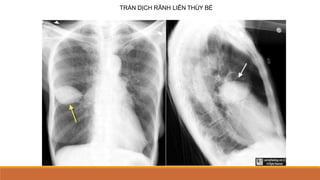

TDMP KHU TRÚ

◦ TRÀN DỊCH RÃNH LIÊN THÙY: BÓNG MỜ HÌNH THOI, HAI ĐẦU NHỌN, Ở

VỊ TRÍ RÃNH LIÊN THÙY 



HÌNH ẢNH GIẢ U HAY U MA, MẤT ĐI SAU ĐIỀU

TRỊ (PB VỚI U)

TRÀN DỊCH RÃNH LIÊN THÙY BÉ